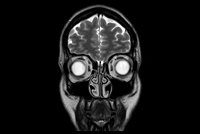

dS Head 32ch - Pituitary